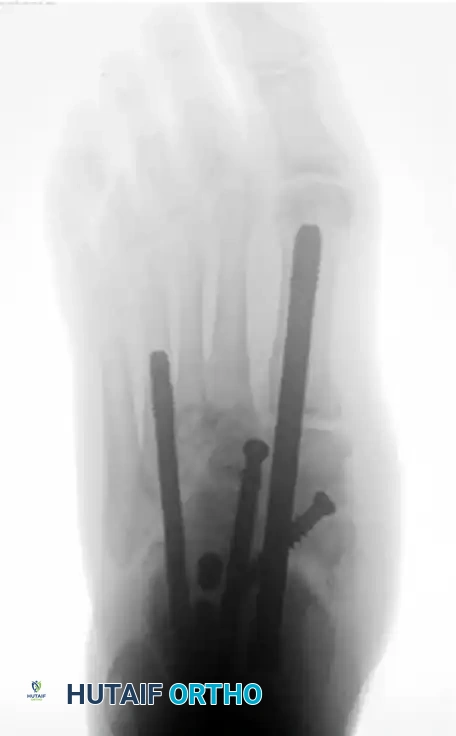

Forefoot Charcot arthropathy similarly requires meticulous realignment and often extended fusions or resections to prevent recurrent ulceration beneath prominent metatarsal heads.

Image

FIGURE 85-24 A and B: Radiographic examples of advanced Charcot arthropathy affecting the forefoot, requiring complex realignment to restore a braceable architecture.